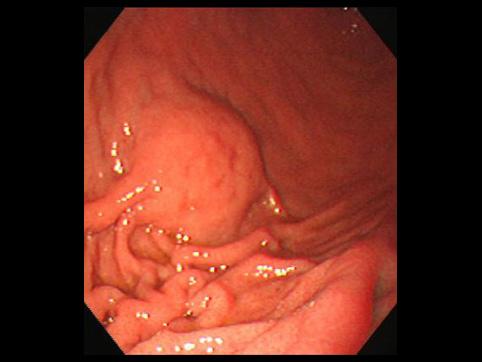

점막하 종양만의 형태를 나타낸 융기형의 위 MALT 림프종

[Image-ID:10253]

악성 림프계종양/악성 림프종

위(부위)/체부

내시경

1형(종괴형)/

35~40

mp